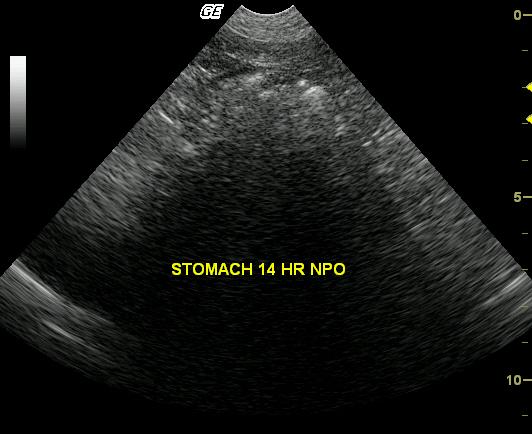

This 9-year-old MN Boxer was presented for retching, hyporexia, and foul halitosis. The physical exam, CBC, blood chemistry, and urinalyses were all normal. The dog presented 14 hours postprandial of 1 can of i/d diet. The patient had been empirically treated with amoxicillin and metronidazole for presumed Helicobacter gastritis with partial response over a 3 week protocol.